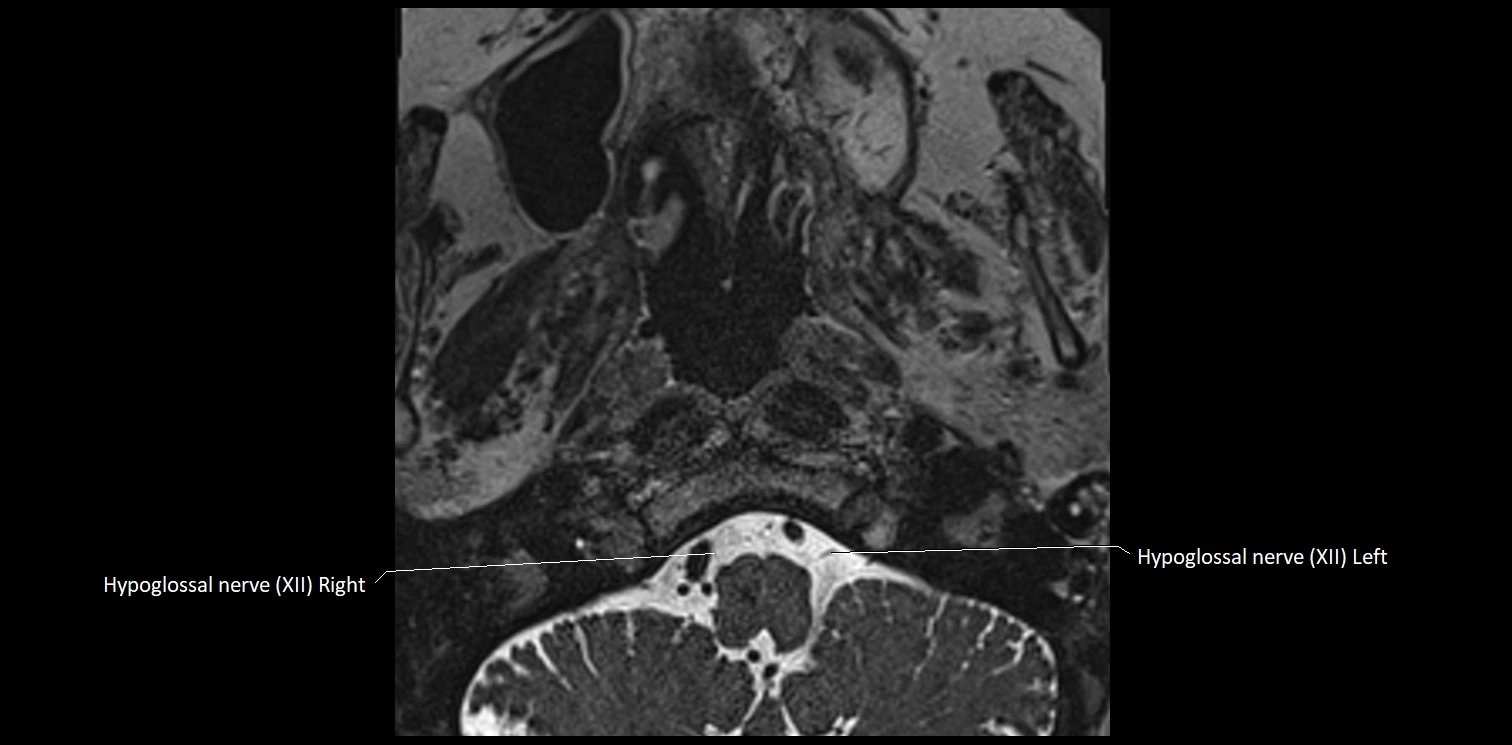

MRI Appearance

• The abducens nerve is a small, thin, linear structure

• Best visualized on high-resolution T2-weighted 3D MRI sequences (e.g., FIESTA or CISS)

• Seen as a hypointense (dark) line running from the brainstem at the pontomedullary junction, traversing the prepontine cistern, and entering Dorello’s canal under the petrosphenoidal ligament, then into the cavernous sinus, and finally the orbit

• May be challenging to visualize in standard MRI due to its small size

• Pathology may be inferred by absence, displacement, or enhancement of the nerve

MRI images

image